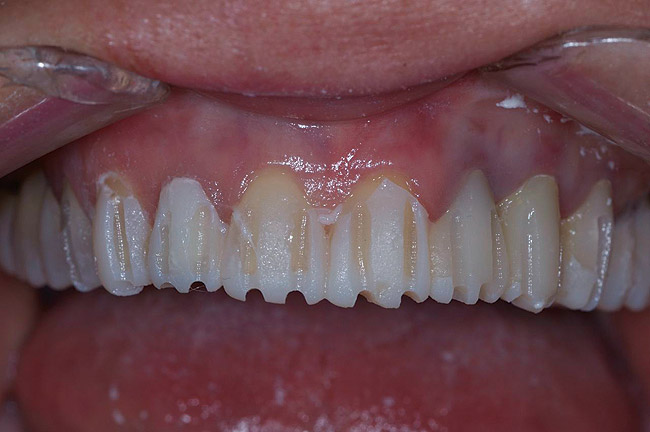

Figure 30  Final restorations.

Figure 30

Figure 31  Technical precision and artistic skill blend into a pleasing smile and a happy patient.

Figure 31